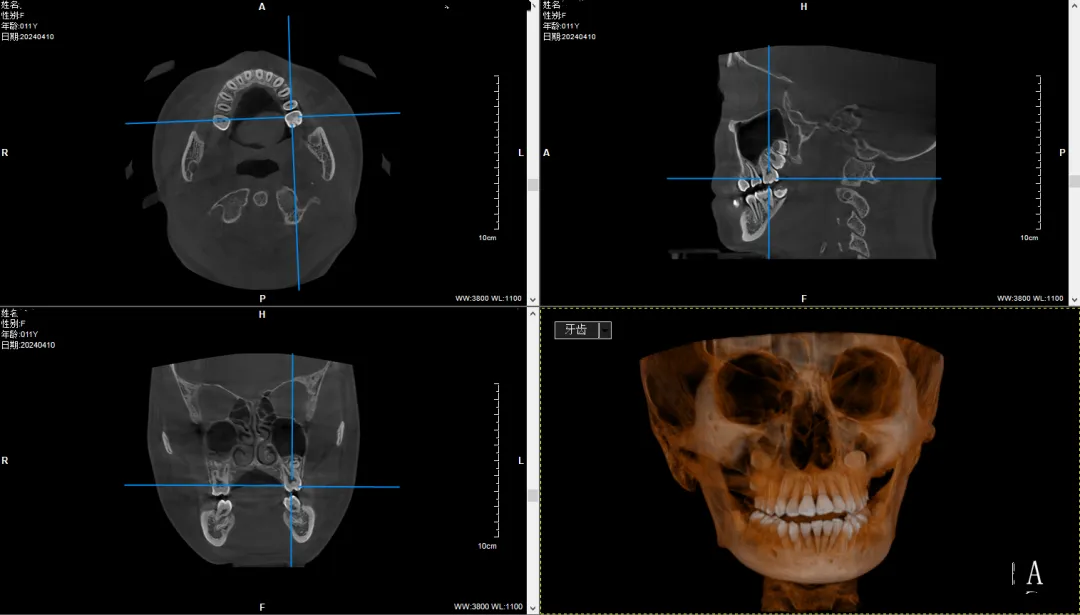

皓月2.0五合一CBCT,为儿牙健康护航

作为朝阳总院的焕新之选,皓月2.0以低辐射高质量成像方案和诸多人性化细节,为更多家庭带来高品质的诊疗服务,也见证着南京瑞德医疗与袁林天儿童口腔的志同道合,同心同行。

儿童对辐射的敏感性是成人的 2~3 倍,要更好的关爱儿童口腔健康,降低拍摄辐射是必须解决的问题。皓月2.0采用脉冲式曝光,一次扫描非拼接成像,配合自研的Ldirara(LDira reconstruction algorithm)AI低剂量算法,儿童最低只需70kV-2mA剂量,即可完成有效诊断影像的拍摄,辐射量远低于行业平均水平,能更好的保护患者与医护人员。

超强性能,更高效

医院容量有限,要让更多的儿童获得高水平的治疗,提高运行的效率同样至关重要。皓月2.0同时具备CT、全景、侧位、小牙片拍摄功能,医生可以根据患者实际情况,灵活选择需要拍摄的各类影像。采用超低剂量拍摄,可以有效降低设备的运行压力,算法与硬件协同之下,CT可连续拍片200组,患者无须长时间等待,更加契合超大客流就诊需求。

瑞德医疗自构底层框架、融合了多重AI技术的“智影”后处理软件、“慧影”正畸软件,带来自动绘制双侧下颌神经管、区域骨密度测量、骨龄分析、可联动术前术后比对、AI牙弓线精准绘制、一键获取影像图片、多种报告等功能,进一步提升诊疗的效率与便捷性。